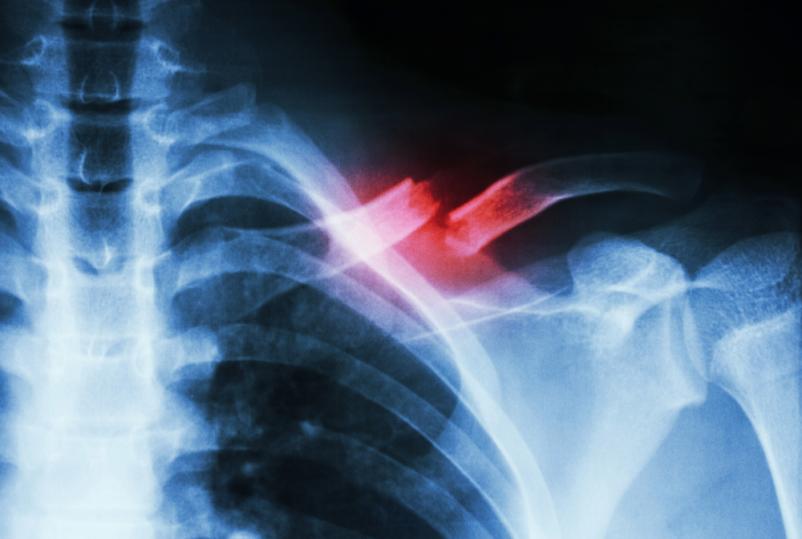

Rentgensko slikanje skeleta je ena osnovnih in najpogosteje uporabljenih diagnostičnih metod v medicini. Omogoča hiter vpogled v stanje kosti, sklepov in drugih struktur ter je nepogrešljivo pri sumu na zlome, degenerativne spremembe ali druge poškodbe. Prav zato je rentgen skeleta brez naročanja izjemno pomembna prednost, saj pacientom omogoča, da so obravnavani pravočasno in brez dodatnega stresa.

Storitev zajema slikanje različnih delov skeleta, pri čemer se uporablja sodobna rentgenska oprema, ki zagotavlja kakovostne in natančne posnetke ob hkratnem upoštevanju vseh varnostnih in strokovnih standardov. Postopek je hiter, neboleč in ga izvajajo izkušeni zdravstveni delavci, usposobljeni za delo na področju radiološke diagnostike.